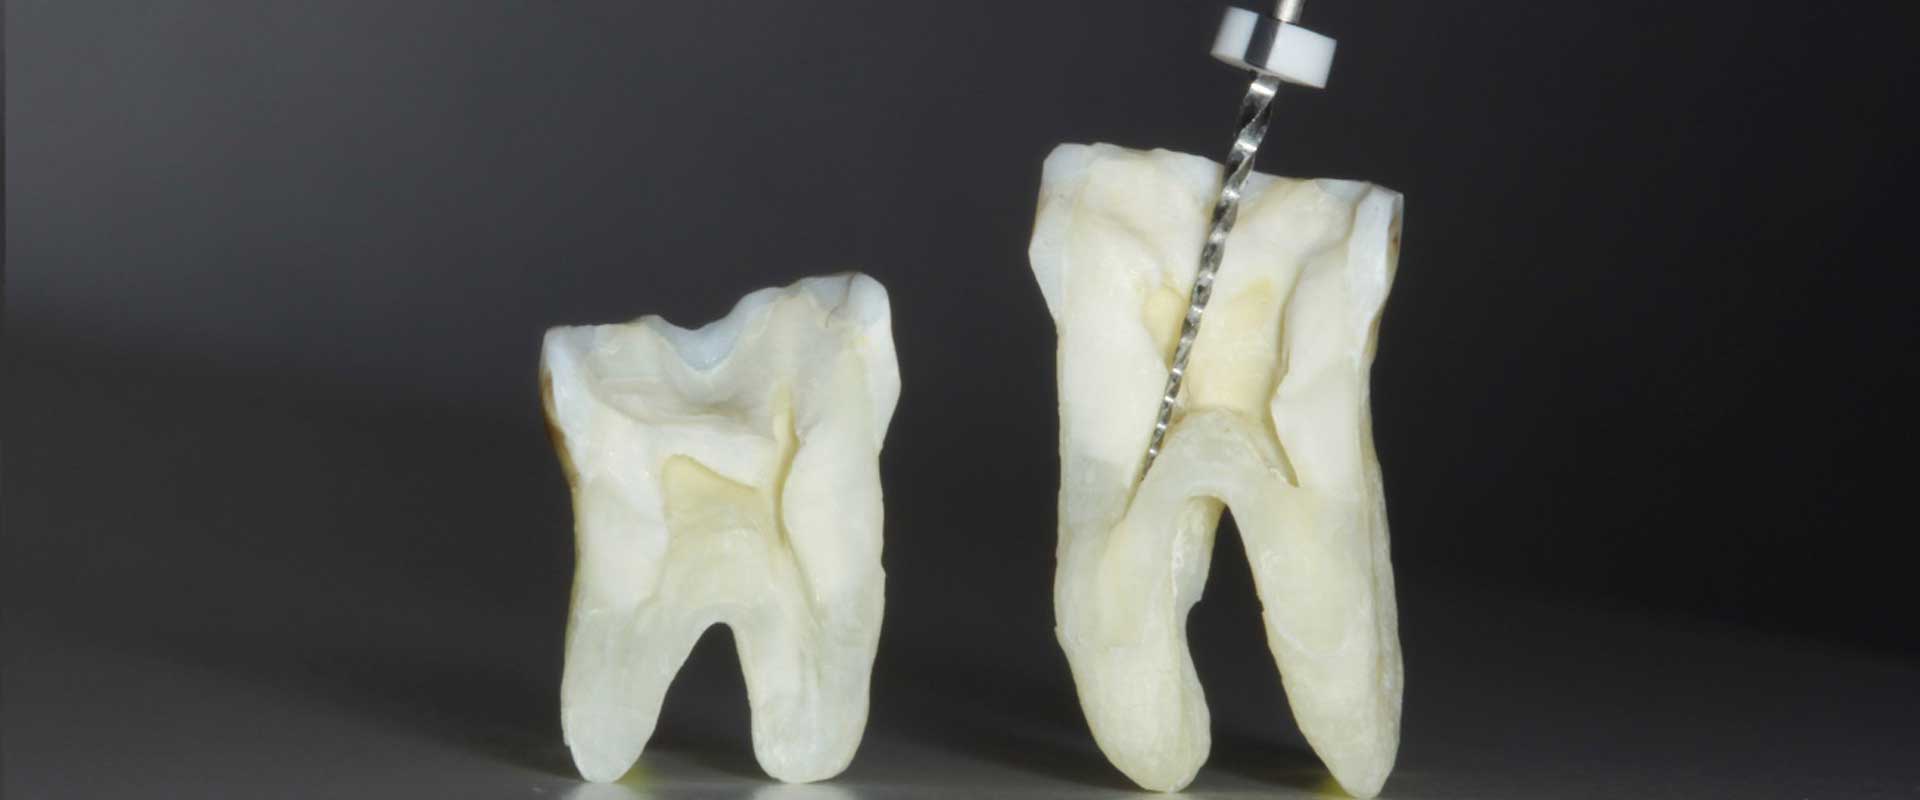

La endodoncia consiste en la remoción del tejido pulpar del interior de la cámara y los conductos de las raíces dentales. Para ello utilizamos una serie de limas, mediante un sistema rotatorio, de diferentes diámetros ensanchando los conductos y otorgándoles cierta conicidad para, posteriormente, rellenarlos y que queden sellados no permitiendo el paso de bacterias desde la boca al hueso y los tejidos que lo rodean.